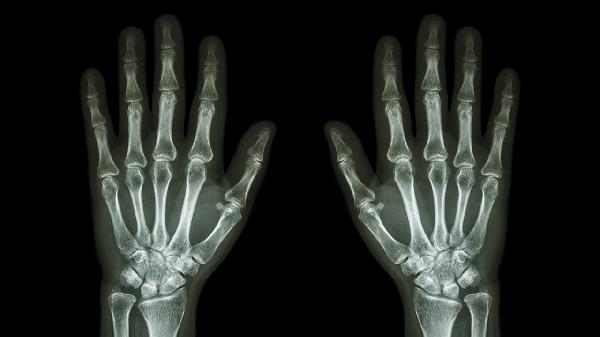

手指指关节疼痛是什么原因引起的

手指指关节疼痛可能由骨关节炎、类风湿关节炎、痛风性关节炎、外伤或腱鞘炎等原因引起。